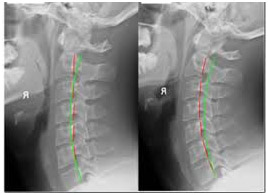

위의 두 엑스레이는 조금더 심각한 상태의 거북목 증후군 환자의 사진인데요. 거북목 환자의 교통사고 전후를 비교해 놓은 사진 입니다. 왼쪽 사진은 일자목 상태의 교통사고 전이 상태이고 오른쪽은 교통사고 후의 상태 입니다. 보시면 아시겠지만 이미 거북목 증후군을 앓고 있는 분이 교통사고가 났을때는 조금서 심각한 문제를 초래 할수 있습니다. 오른쪽 사진에서 보듯이 커브가체가 아예 역으로 변형이 되어 버린 상태입니다. 이러한 상태는 사고로 인해 목뼈 뒤분을 잡고 있는 인대의 손상과 뼈사이사이의 디스크 손상을 동반한 상태 입니다.